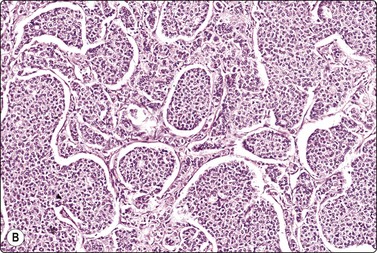

Phyllodes tumor (Figs 7.29-7.32)117-123

Phyllodes tumor (PT) is a biphasic epithelial/stromal neoplasm of the breast. In contrast to fibroadenoma, PT is a rare tumor comprising less than 0.3% of all breast tumors. It is classified as benign, low grade (borderline) and high grade (malignant) based on histologic features. Stromal cellularity and overgrowth, atypia, mitotic activity, and invasive growth pattern at tumor periphery define whether a PT is benign, low grade or high grade. Benign PTs do not metastasize, but may locally recur if incompletely excised. High-grade PTs behave like sarcomas with higher potential for recurrence and metastasis. Low-grade PTs fall in between.

image image

Fig. 7.29 Benign phyllodes tumor

(A) Huge, slowly growing breast mass in a 40-year-old woman; (B) FNB smears were cellular, dominated by dispersed cells with bare oval or plump spindle nuclei (MGG, HP).

Fig. 7.30 Borderline phyllodes tumor

Smears dominated by mildly atypical, both plump and slender spindle cells, single and in loose tissue fragments with fibrous stroma; a few sheets of bland duct epithelium (A, MGG; B, Pap, HP).

Fig. 7.31 Malignant phyllodes tumor

(A) Mainly dispersed spindle cells showing moderate nuclear atypia, no epithelial cells. Invasive growth demonstrated in tissue sections; multiple recurrences (MGG, IP); (B) Another case showing numerous spindle cells with more marked atypia and a sheet of bland epithelium (Pap, HP).

image

Fig. 7.32 Fibroadenoma mimicking benign phyllodes tumor on core needle biopsy (H&E, IP).

Aspiration biopsy can accurately diagnose malignant PTs in most cases. On the benign/borderline end of the spectrum, cytologic features of fibroadenoma and PT overlap, making FNA diagnosis difficult (see Fig. 7.23). Precise preoperative distinction is important for optimal patient management. Classic cytologic features in PT are similar to fibroadenoma. However, as opposed to fibroadenoma, stromal fragments are larger, increased in number (stromal overgrowth) and are hypercellular (phyllodes fragments); the single stromal cells in the background are plumper than the typical oval bare nuclei seen in fibroadenoma. These single cells are intact spindled cells with retained cytoplasm (not naked nuclei), and variable degrees of nuclear atypia with nucleoli and pleomorphism. However, some of these features may be entirely lacking in benign and low-grade PTs even after retrospective review of smears, making their differentiation from fibroadenoma virtually impossible. It is not surprising that a considerable portion of benign and low-grade PTs are initially diagnosed as fibroadenoma on cytology.117,120,121 This in part reflects sampling problems as hypo- and hypercellular areas tend to alternate within PTs. Another important diagnostic pitfall in PTs is the presence of significant epithelial proliferation including atypical ductal epithelial hyperplasia. If these areas are sampled by aspiration biopsy, this may lead to a false diagnosis of epithelial neoplasm. In our experience, we encountered this problem even with high-grade (malignant) PTs; one such retroareaolar case required core biopsy due to inability of aspiration biopsy to rule out an atypical papillary lesion. In addition, focal malignant transformation may be missed by FNA sampling.

The diagnosis of PT on CNB is equally as challenging (Fig. 7.32). It is especially difficult to differentiate cellular fibroadenoma from benign/low-grade PT. In comparison, in one study, the possibility of PT was raised in 23% on FNB and 65% on core biopsy.122 In two others, 11 of 44 (25%), and 9 of 23 (39%) of surgically resected PTs were reported as fibroadenoma or benign on core biopsy.123,124 Similar to FNB, some PTs are diagnosed as fibroadenoma on core biopsy because of tumor heterogeneity. Marked nuclear pleomorphism and mitotic activity suggest frankly malignant phyllodes tumor (Fig. 7.31A,B).